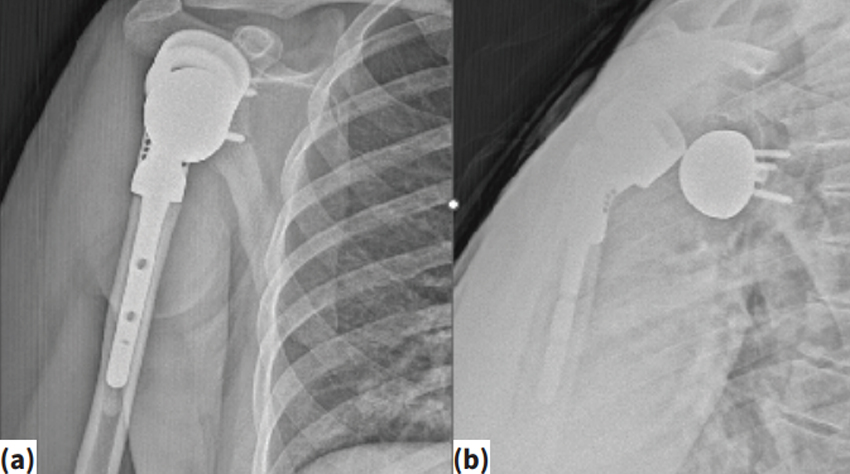

Более...Omuz çevresi tümörlerde ters omuz proteziReverse shoulder prosthesis for tumors around the shoulderVolkan Gürkan1 , Muzaffer Ağır2 , Fatih Yıldız3 1 Avicenna Umut Hastanesi, Ortopedi ve Travmatoloji Kliniği, İstanbul 2 Acıbadem Üniv...